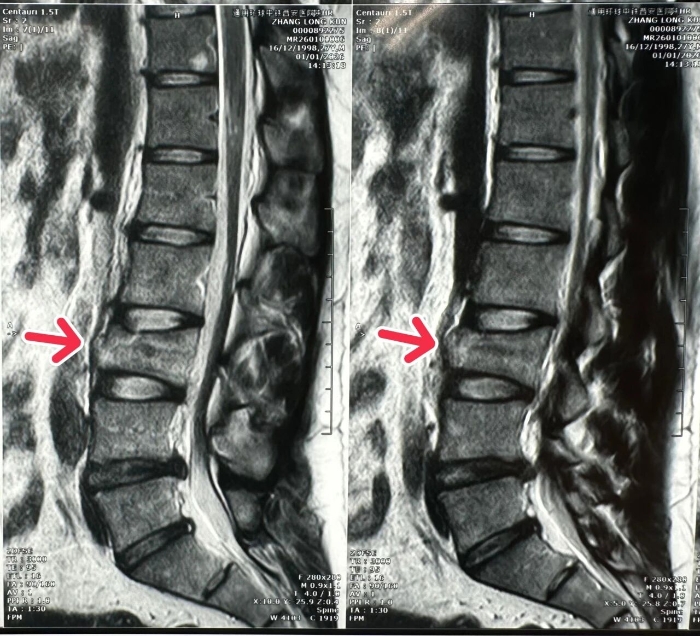

面对这位腰椎骨折伴神经损伤、随时可能因神经受压加重导致永久性残疾的患者,骨科姬传磊主任立即牵头组建急诊手术团队。影像科、麻醉科、手术室等多部门同步联动,在极短时间内完成腰椎CT、MRI等关键检查,明确损伤情况并排除手术禁忌,为后续手术争取了宝贵时间。

在姬主任的带领下,手术团队为患者施行了“腰椎骨折切开复位内固定+椎管减压术”。手术通过小切口精准操作,有效解除了骨折对脊髓神经的压迫,并实现了骨折椎体的复位与稳定固定。整个手术过程顺利,患者生命体征平稳,术后患者神经刺激症状显著缓解,安返病房。